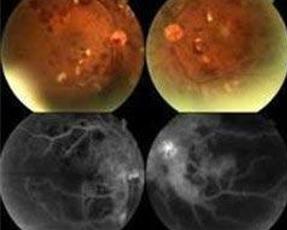

放射性视网膜病变临床变异较大,但发病呈剂量相关的特点。轻微的放射性视网膜病变的早期临床特点可以见到眼后极部出现分散的小的毛细血管阻塞病灶,病灶周围的毛细血管不规则扩张,严重的放射性视网膜病变常常发生在远程放疗没有进行很好的眼部保护时,眼底有广泛的毛细血管闭锁和视网膜血管异常,可以导致黄斑水肿、渗出和视力下降。